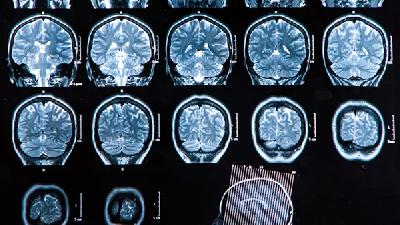

脑萎缩的可能原因